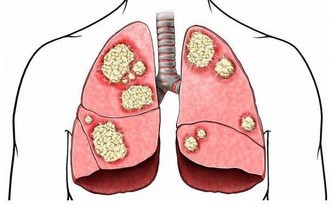

血管硬化是指血管瀰漫性粥樣硬化、管腔狹窄及小血管閉塞致使腦部血供減少所引起的一系列病理變化。許多老年人都有不同程度的血管硬化現象,血管硬化的主要原因也就是動脈硬化導致,它是由於輸送血液的血管發生了硬化,造成了血管狹窄或閉塞,導致局部組織得不到充足的氧氣和營養,致使組織缺氧和壞死,可發生於全身各個部位。